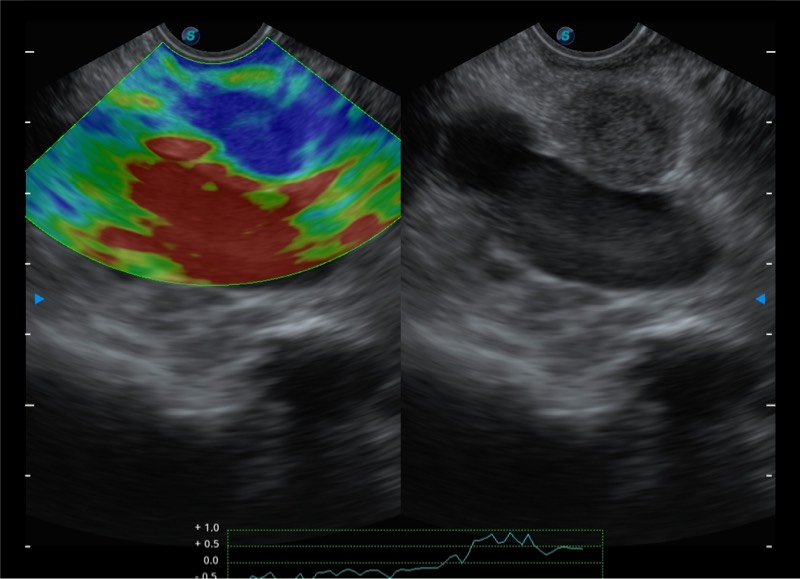

搭载百万级CMOS成像技术

及自主研发凸阵换能器,

可呈现优质的内镜和超声画面

基于二十年的超声技术积累,百老汇电子游戏官网提供了最新一代的独立超声主机,在提供高质量图像的同时满足多学科使用。具备常见多普勒技术并提供弹性成像、声学造影等高端影像技术。新一代传感器具有更强的抗干扰能力并减少图像伪影。

4-12MHZ宽频输出